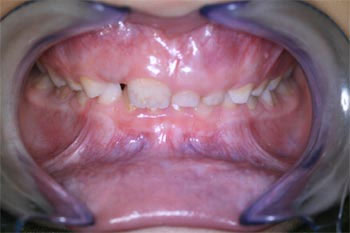

Скученность зубов во фронтальном отделе нижней челюсти.

Аномалия II класса 1 подкласса Энгля в сочетании с глубокой резцовой дизокклюзией

Открытый прикус во фронтальном отделе

Аномалия II класса 2 подкласса Энгля в сочетании с глубокой резцовой дизокклюзией (вследствие нижнечелюстной ретрогнатии)